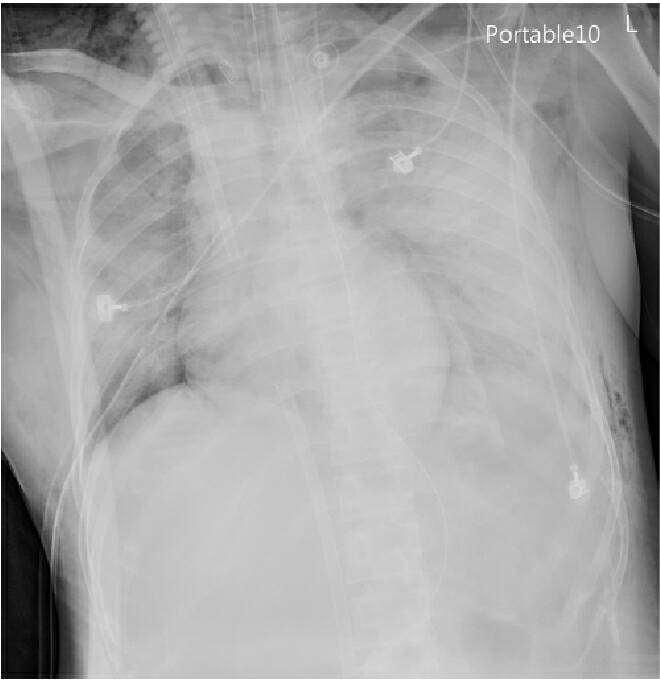

婦人的X光顯示肺部已大片泛白嚴重浸潤、衰竭(示意圖)

近期寒流連番來襲,感冒患者與日俱增,宜蘭縣一名45歲婦人因發燒、咳嗽服藥1個月未見改善,至醫院X光檢視,發現其肺部已大片泛白嚴重浸潤、衰竭,經緊急於24小時內幫婦人裝置葉克膜,歷經20幾天搶救,才將婦人從鬼門關拉回。

在接受治療後,原肺部發炎的泛白已消失無蹤(示意圖)